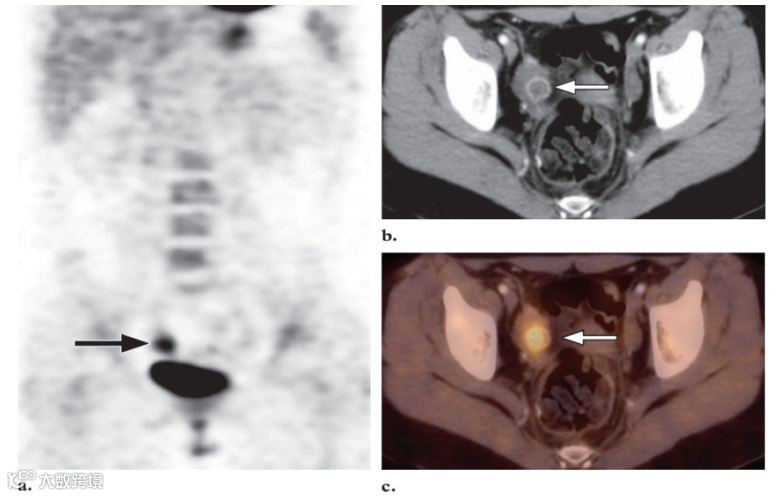

图12. 一名15岁女孩的良性卵巢18F FDG 摄取,该女孩有腹部大B细胞淋巴瘤病史。

冠状18F FDG PET 扫描 (a) 和轴位融合PET/CT图像 (b) 显示双侧卵巢FDG摄取增高灶 (箭头),与月经中期排卵有关。随访成像显示摄取增高灶消退。

图13. 一名17岁女孩的卵巢黄体囊肿,该女孩有IVB期霍奇金病病史。患者最近一次月经发生在完成化疗后接受FDG PET/CT 随访前3周。

(a)冠状FDG PET 扫描显示骨盆右侧局部摄取增加(箭头)。

(b)横向CT扫描显示右卵巢有囊性结构,边缘增强(箭头),这一发现与卵巢黄体囊肿一致。

(c)横向融合PET/CT图像显示囊肿局部摄取增加(箭头)。